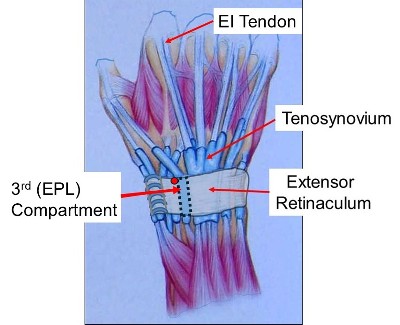

- The muscles are in the forearm. Tendons are like rope joining the muscles to the fingers and thumb. There is a strap of tissue ( extensor retinaculum) on the back of the wrist that holds the tendons down. There are 6 tunnels on the back of the wrist containing the Extensor tendons to the thumb, fingers & wrist.

- The Tunnels are lubricated by the fluid produced by a thin layer of tissue called synovium.

- Synovium around a tendon is called Tenosynovium

- EPL Decompression - Removing the EPL from the groove adjacent to Lister’s tubercle & placing it superficial to the retinaculum